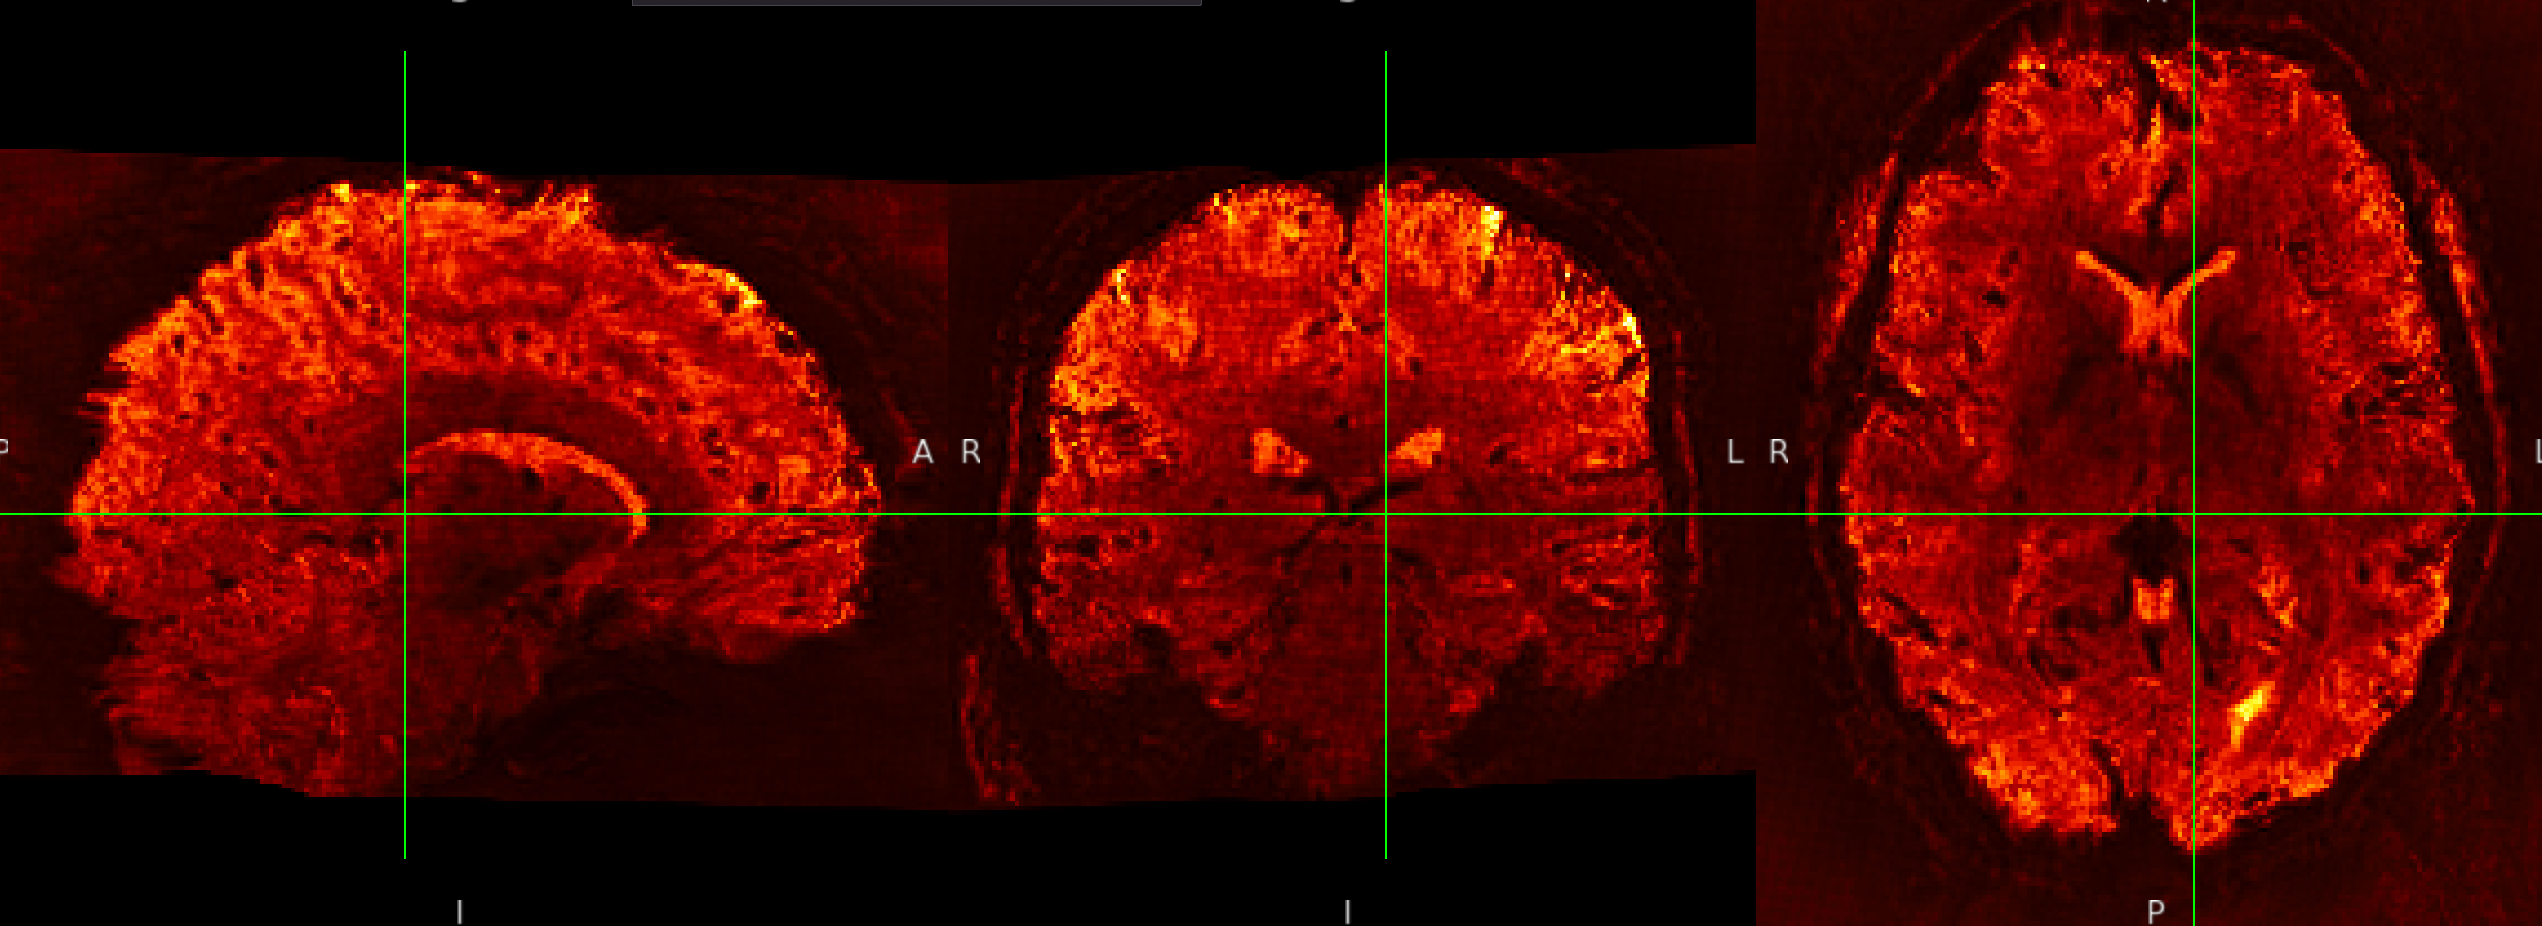

SE sequence in MNI152NLin6Asym-res1

The checkerboard pattern is more evident in the ME sequence where it is also visible outside the brain, but it is present in both, ME and SE inside the brain.

- why is this pattern visible only at MNI 1mm resolutions? Please remember that my voxels are between 1.2 and 1.5 mm isotropic.

- Could this be related to the Lanczos interpolation?

- why is the pattern exacerbated in the ME sequence? Is it the echo combination?